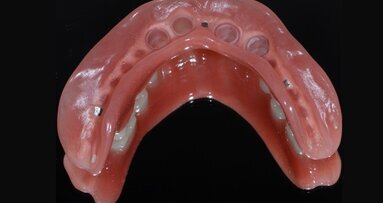

Na kolejnej wizycie, po zdjęciu korony akrylowej, okazało się, że mamy do czynienia z zębem stożkowatym średniej wielkości, wolnym od próchnicy. Pacjentka zdecydowała się na rekonstrukcję metodą bezpośrednią. Resztki cementu zostały delikatnie (tak aby zachować maksymalną warstwę szkliwa) usunięte za pomocą wiertła diamentowego. Następnie powierzchnię zęba wypiaskowano piaskarką abrazyjną. Kolejne etapy odbudowy i efekt końcowy przedstawiają zamieszczone w ryciny.

Do odbudowy bezpośredniej wykorzystano materiał Empress Direct firmy Ivoclar Vivadent oraz podbarwiacze tego samego producenta. Jest to system spójny i łatwy w zastosowaniu, dający przewidywalne efekty.

Dzięki naturalnej transparencji mas szkliwnych, właściwemu, głębokiemu wysyceniu barwą mas zębinowych oraz wysokiej polerowalności sprawdza się w przednim odcinku łuku zębowego o wysokich wymaganiach estetycznych. Autorka używa tego materiału od czasu jego polskiej premiery (wrzesień 2010), obserwując stabilne utrzymanie osiągniętych efektów.